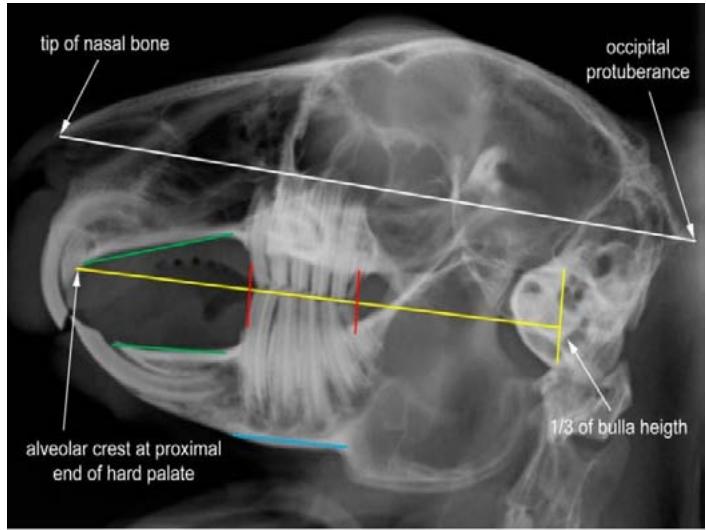

O exame da cavidade oral de roedores e coelhos domésticos faz parte de todo exame físico e é muito importante para o diagnóstico da síndrome do desgaste dentário inadequado, que leva ao hipercrescimento dentário e consequentemente a problemas sistêmicos, no entanto, o exame oral em um animal consciente fornecerá apenas informações limitadas. O exame oral definitivo só pode ser realizado sob anestesia geral SOARES, Helena Baggio (2018). Tem havido inúmeras publicações nas últimas duas décadas descrevendo alterações patológicas específicas observadas nas diferentes espécies. Muitos deles apontam a importância de um exame radiográfico completo do crânio usando múltiplas visualizações e dão alguns conselhos úteis sobre o tratamento, como o uso de linhas de referência anatômicas que simplificam muito a explicação dos problemas bucais aos proprietários do animal (Fig. 2 e 3), pois eles podem ver claramente a extensão das alterações. Isso permite que eles entendam melhor as recomendações de tratamento e quaisquer complicações associadas BOEHMER, E (2009). Ao incluir a radiografia como ferramenta diagnóstica, o número de pacientes relatados que sofrem de má oclusão causada por diferentes alterações periodontais e dentárias patológicas chega a até $88\%$ da população clínica geral BOEHMER, Christine (2020).

Fig. 2: Linhas de referência anatômicas radiográficas de um coelho clinicamente saudável. Vista Latero Lateral.

Fig. 3: Linhas de referência anatômicas radiográficas de um coelho clinicamente saudável. Vista Dorso Ventral.

Foi realizado a coleta de sangue para exames laboratoriais e o paciente foi encaminhado para estudo radiográfico do crânio, onde foi requisitado três projeções a saber: rostro caudal, ventro dorsal e latero lateral (Fig. 8, 9 e 10) e analisado de acordo com BOEHMER, E, 2009 as linhas de referência anatômica para a espécie fechando o diagnóstico de má oclusão dentária pordesgaste ineficiente.

Fig. 8: Radiografia de crânio projeção rostro caudal. Visualização de pontas dentárias evidenciadas pelas setas vermelhas Fig. 9: Radiografia de crânio projeção dorso ventral. Leve desalinhamento dentário na borda medial do ramo mandibular direito, sobrepuljando a linha de referência anatômica amarela, evidenciado em vermelho Fonte: Arquivo pessoal do autor Fig. 10: Radiografia de crânio projeção latero lateral visualização de crescimento dentário dos pré molares e molares sobre a mesa oclusal (linha amarela ${ \mathsf { n } } ^ { \mathsf { o } } \ { \mathsf { 1 } } \ -$ traçada do início do palato duro ao terço inferior da bula timpânica) e também visualização de crescimento da coroa de reserva acima da linha amarela $\mathsf { n } ^ { \circ } \mathsf { \Lambda } _ { 2 } ^ { }$ que vai do osso nasal ao osso occipital (sugerindo crescimento retrógrado), evidenciado pelas setas vermelhas.